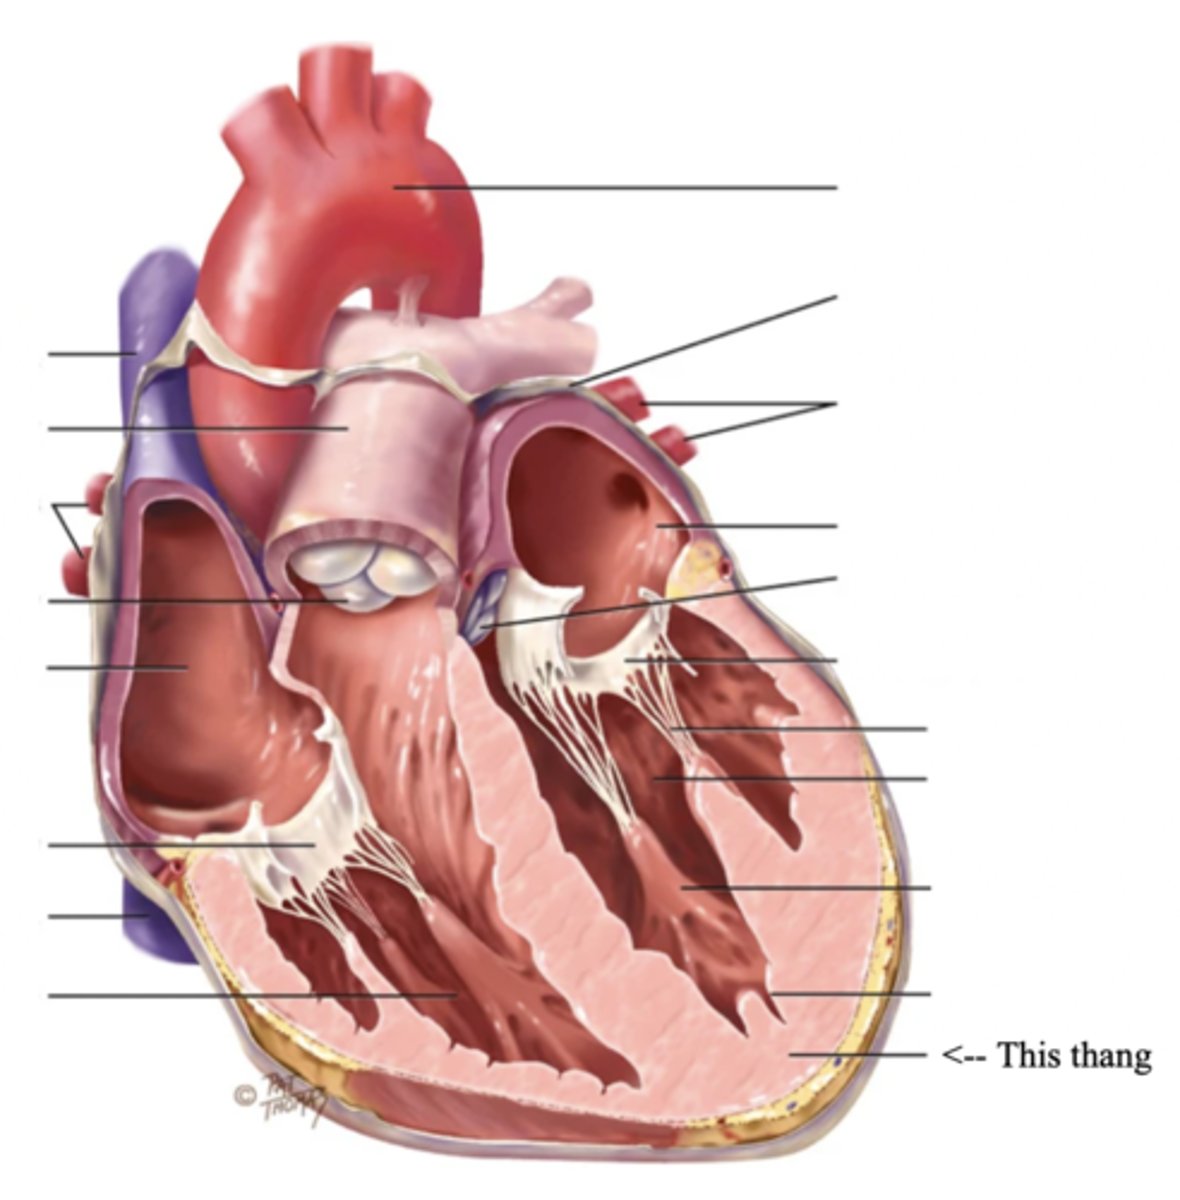

Anatomy of the Heart

3 Layers of the Heart Wall

- Pericardium

- Myocardium

- Endocardium

Pericardium

Myocardium

The muscular wall of the heart; does the pumping

Endocardium

The thin layer of endothelial tissue that lines the inner surface of the heart chambers and valves

2 Types of Chambers in the Heart

- Atrium

- Ventricles

Atrium (2)

A thin-walled reservoir for holding blood, located at the upper chamber of the heart

Ventricle (2)

The thick walled muscular pumping chamber of the heart located at the bottom chamber of the heart

2 Main Types of Valves of the Heart

- Atrioventicular

- Semilunar

Atrioventricular Valves (AV) (2)

The valves that separate the atria and the ventricles

The 2 Atrioventicular Valves of the Heart

- Tricuspid

- Mitral

Tricuspid Valve

- The right AV valve separating the right atrium from the right ventricle

- Connected by 3 chordae tendinae

Mitral (Bicuspid) Valve

- The left AV valve separating the left atrium from the left ventricle

- Connected by 2 chordae tendinae

Chordae Tendinae

Fibers (heart strings) attatched to the tricuspid and mitral valve which pull it closed when papillary muscles contract, preventing back flow of blood

Semilunar Valves (SV) (2)

Valves located between the ventricles and the pulmonary arteries and aorta

The 2 Semilunar Valves of the Heart

- Pulmonic

- Aortic

Pulmonic Valve

The SV valve of the right side of the heart

Aortic Valve

The SV valve of the left side of the heart

The 4 Great Vessels of the Heart

- Superior/inferior venae cavae

- Pulmonary artery

- Pulmonary veins

- Aorta

Superior/Inferior Venae Cavae

The large veins that empty into the right atrium of the heart and return unoxygenated venous blood to the right side of the heart

Pulmonary Artery

Artery carrying oxygen-poor blood from the heart to the lungs

Pulmonary Veins

Veins carrying oxygenated blood from the lungs to the heart

Aorta

The largest artery in the body which carries oxygenated blood from the heart throughout the body